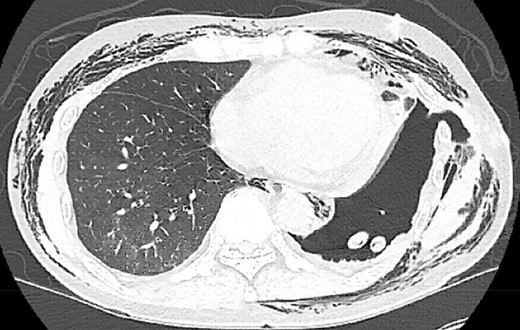

The patient underwent multiple procedures to mitigate the air leak from his peripheral BPF including image-guided 12 Fr. pigtail placement, endobronchial valve placements down the left upper and lower lobe segmental bronchi, and autologous blood patching through the thoracostomy tube. He was treated for associated Aspergillus pneumonia and eventually discharged with stable hydropneumothorax. The patient was readmitted multiple times for chest-wall infection and pneumonia. He underwent OWT via Clagett procedure 5 months after his index operation. Chronic fibrosis and purulent effusion were noted with an air leak at the left upper lobe apex. He was discharged home on POD 23 with wet-to-dry dressings and with an 8-week course of antibiotic and antifungal medication (Fig. 3).